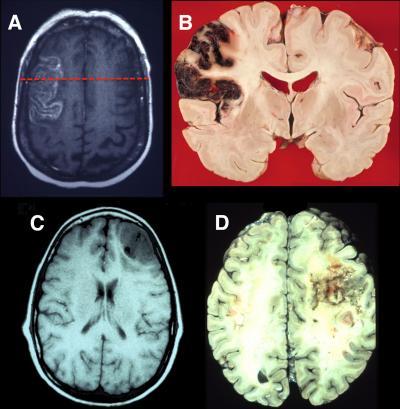

(A) This is an axial T2 magnetic resonance imaging (MRI) image showing an acute stroke in the left lateral prefrontal cortex. (B) This is a coronal neuropathological specimen of an infarct in the left lateral PFC (note the hemorrhagic conversion in the cortical mantle). The red dashed line on the MRI in (A) shows the approximate site of the postmortem coronal slice. (C) This is an axial T1 MRI image showing infiltrating glioblastoma in the right lateral frontal cortex. (D) This is a postmortem axial slice of an infiltrating glioblastoma in the right lateral frontal lobe. Neuropathological specimen in (B) compliments of Professor Dimitri Agamanolis, Akron Children's Hospital.

(Photo Credit: Neuron, Szczepanski et al.)